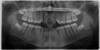

Cherubism

- presents in Kids

- multiple quadrants of CGCL

- often resolves in adulthood, sometimes not.